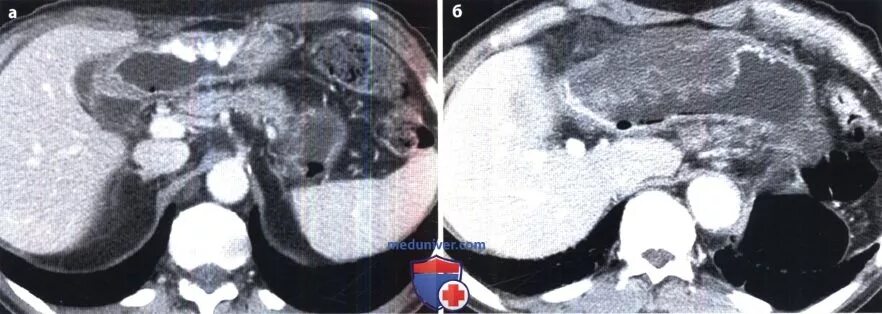

Язва желудка кт